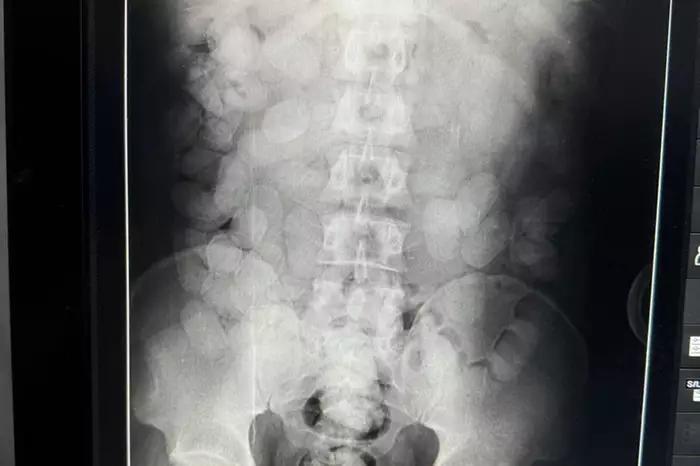

Um paraense que tentou embarcar com cerca de 70 cápsulas de cocaína no estômago l, com destino à França e foi preso na manhã desta terça-feira (09/07), no Aeroporto Internacional de Belém. Abordado pela Polícia Federal, ele confessou a intenção de tráfico internacional de drogas, passou por raio-X no Hospital Metropolitano de Belém.